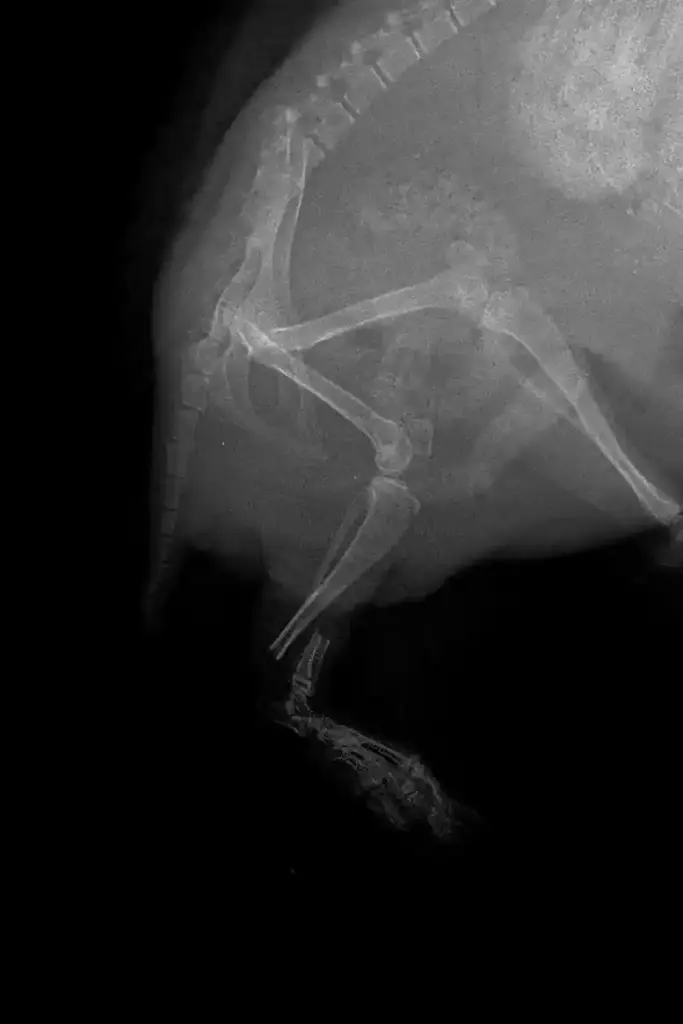

Peg-leg was X-rayed to determine the extent of the damage and the viability of repairing the leg.

Thankfully, she had a clean break, and so the possibility of re-aligning the leg was good! If the fracture had splintered and contained multiple fragments, then securing the bones together would have been a difficult task with the fragility of the remaining bones being an issue.

Meriem had the tedious task of re-aligning Peg-leg’s left tibia, and securing the bones together using a metal pin.